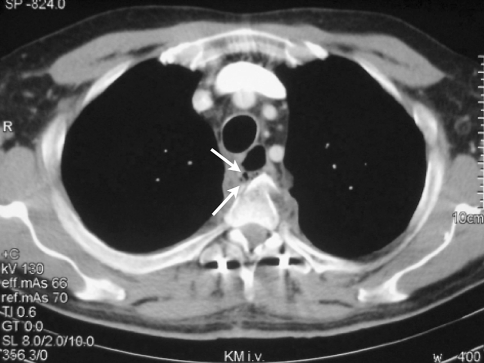

Fig. 2.

Computed tomography of the chest obtained after septic decompensation of the patient with abscess formation and peri-oesophageal air inclusions at the level of the fractured vertebrae